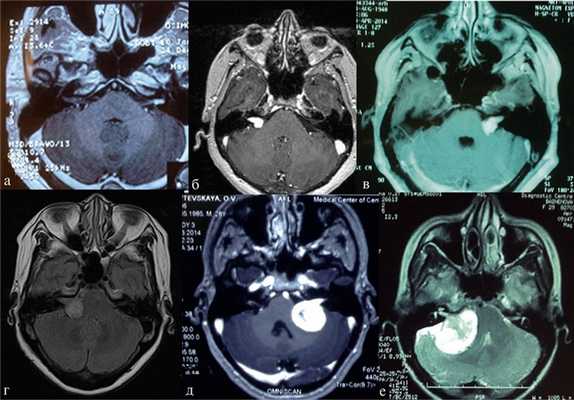

В практической деятельности наиболее универсальными являются классификации, предложенные Koos [11] и Samii [12]. Они основаны на оценке размеров невриномы и ее отношении к окружающим мозговым и костным структурам (рис. 1, 2).

Рис. 2.Классификация неврином слухового нерва по M. Samii. а — Т1 — интрамеатальная опухоль (рис. 2, a); б —Т2 — интра-экстрамеатальная опухоль; в — Т3а — опухоль заполняет мостомозжечковую цистерну; г —Т3b — опухоль распространяется до ствола головного мозга; д —Т4а — опухоль вызывает компрессию ствола; е —Т4b — опухоль грубо деформирует ствол мозга и IV желудочек.

Классификация M. Samii

Т1 - интрамеатальная опухоль.

Т2 - интра-экстрамеатальная опухоль.

Т3а - опухоль заполняет мостомозжечковую цистерну.

Т3b - опухоль распространяется до ствола головного мозга.

Т4а - опухоль вызывает компрессию ствола.

Т4b - опухоль грубо деформирует ствол мозга и IV желудочек.